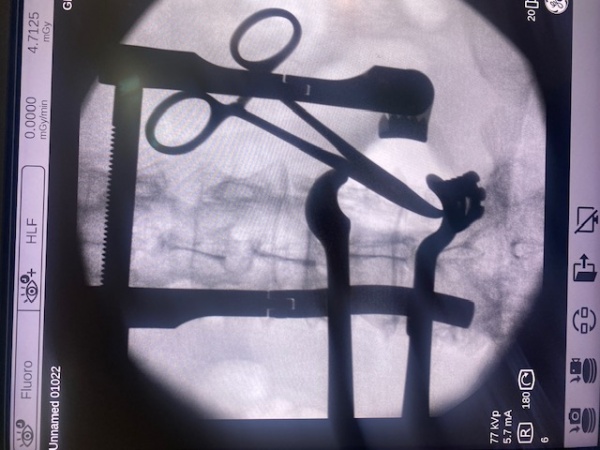

HERNIA DISCAL LUMBAR: en función del caso y las características del paciente, podemos realizar cirugía ENDOSCÓPICA (con unos pequeños orificios y la ayuda de la microcámara eliminamos la hernia discal) o la MICRODISCECTOMIA (una pequeña incisión y la ayuda de un retractor especial para visualización directa y eliminación de la hernia discal). Ambas cirugías tienen una hospitalización corta de 24-48 horas y una recuperación en pocas semanas.

Microdiscectomía lumbar

Microdiscectomia lumbar